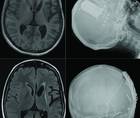

After EBP, refractoriness was demonstrated, all imaging was again reviewed, and the possibility of inadequacy of the cranioplasty flap was considered. It was hypothesized that inadequate covering of calvaria by a defective cranioplasty flap may lead to inward atmospheric force, causing brain sagging syndrome (BSS) and secondary intracranial hypotension.2 Contrast CT of the head showed dural thickening and enhancement at the cranioplasty graft site with improper opposition (Figure 1F). On re-exploration, the implant was found to be fractured into 3 pieces (Figure 2, A to C). Revision and reconstruction of the right frontoparietal cranioplasty using bone cement was performed and fixed with 4 plates.

Figure 2. Cinematic volume-rendered image of the skull shows a porous cement graft with fracture (white arrow) (A). Intraoperative photographs show the broken previous implant (dotted white lines) (B, C). Sagittal 3-dimensional fluid-attenuated inversion recovery MRI scan before surgery (D) and a comparative MRI scan at 3 months after surgery (E) show substantial resolution of tonsillar herniation and improved mammillopontine distance.

LK started to improve immediately and by 15 days after surgery, was able to perform all routine activities. By 3 months after surgery, LK had resumed professional activities, which continue to be maintained to this date. Follow-up CT showed good approximation of bone flap, and MRI showed improvement in signs of intracranial hypotension (Figure 2, D and E). LK has regained independence with no difficulties in speech, swallowing, or gait.